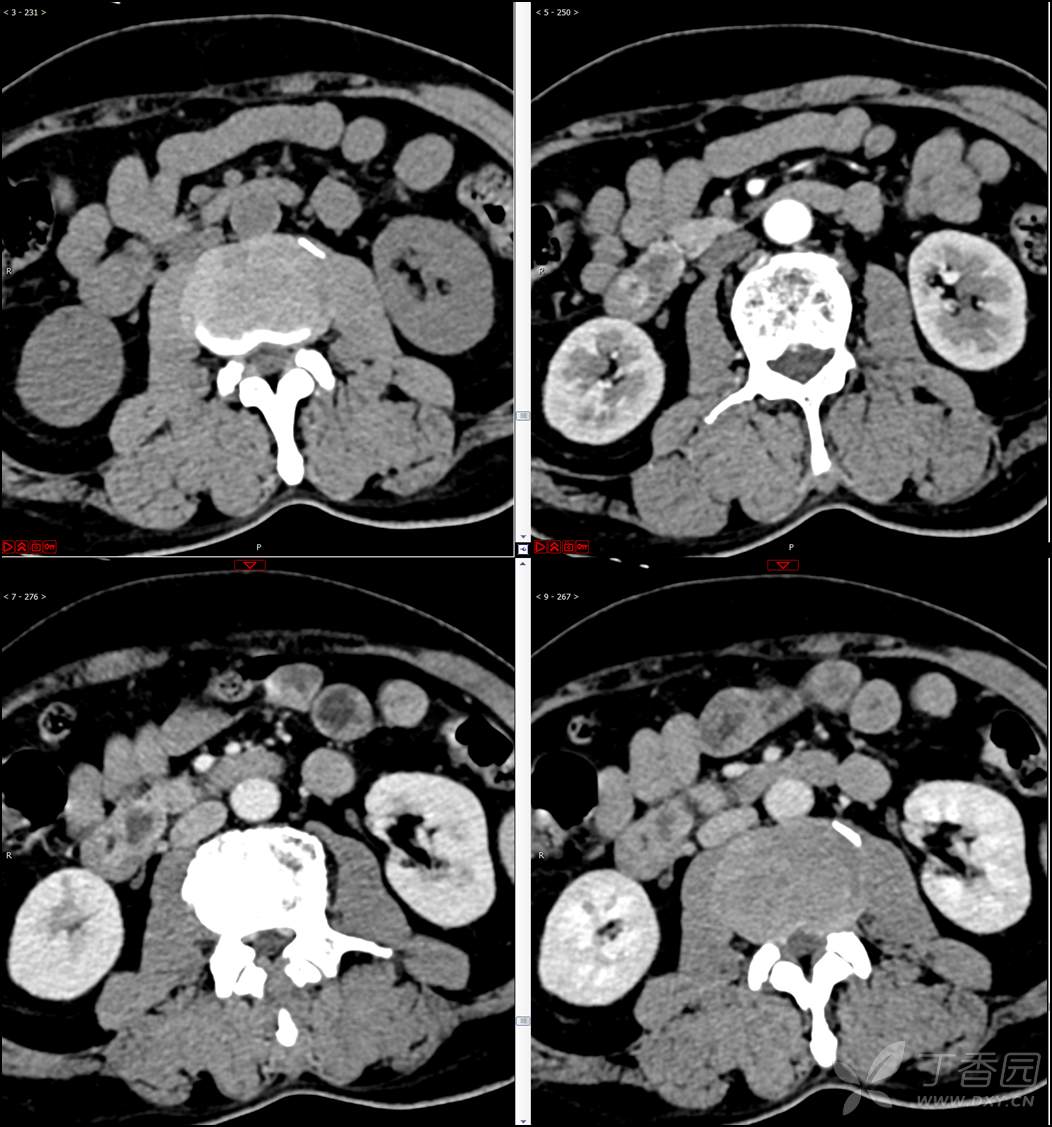

【影诊笔记521】老年男性,黑便就诊,请分析~『回帖即可查阅答案』

患者年龄:67岁

主诉:黑便1周。

现病史:患者1周前无明显诱因出现黑便伴头晕、心慌,无胸闷、胸痛,后仍间断黑便,2022-10-27就诊于某市中医院,行胃镜检查示:十二指肠溃疡伴出血,给予止血、抑酸等对症治疗,效果欠佳。今为行进一步治疗就诊于我院急诊,门诊完善新型冠状病毒核酸检测后以“十二指肠溃疡伴出血”收入我科。患者自发病以来,神志清,精神可,未进食,睡眠可,小便未见异常,黑便,近期体重无明显增减。